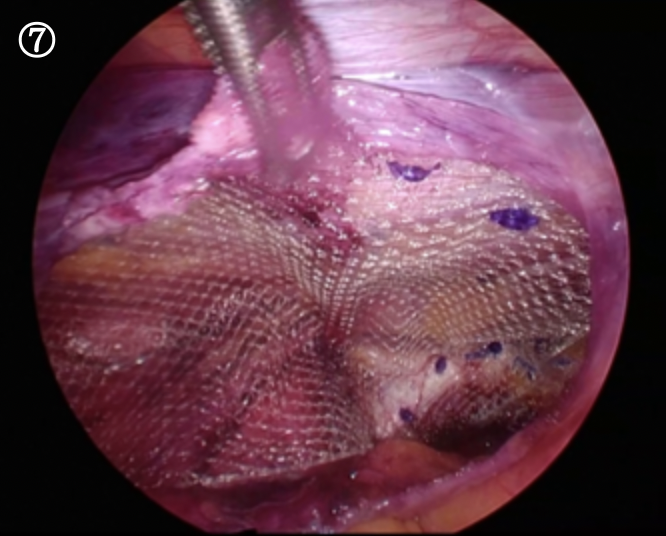

この腹膜をはがしたスペースに人口の布(メッシュ)を入れ広げ、溶けるスクリューねじで固定していきます

血管や神経を避けてねじを打ち込みメッシュを広げた状態です